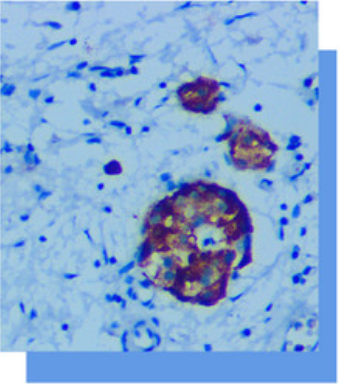

Chromogranin抗体试剂

CgA是肾上腺髓质中-种分子量为68KD的可溶

性酸性蛋白。广泛表达在神经组织以及人内分泌细

胞组成的分泌腺,如甲状旁腺、肾上腺髓质、垂体

前叶腺、胰鸟细胞和甲状腺C细胞。其分布于含有内

分泌颗粒的神经内分泌细胞中,可以用胃肠道粘膜

作为阳性对照组织。CgA联合SYN主要应用于神经

内分泌细胞肿瘤(Apud系统肿瘤)的诊断及鉴别诊断

如垂体肿瘤、胰鸟细胞瘤、肺的小细胞癌、副神

经节瘤、肾上腺嗜铬细胞瘤、甲状旁腺肿瘤、

Merkel细胞癌(小细胞癌阴性)、类癌等。